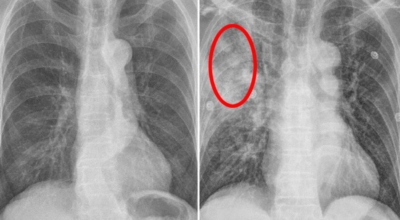

폐암 검사는 X-ray를 통해서 검사하는데 , 크기가 작거나 구석에 위치한 경우 확인이 어려운 경우도 있답니다. 그리고 조직 검사를 통해서 정확한 진단을 하게 돼요. 폐암이 발견되면 종양의 크기나 전이 여부 , 위치에 따라서 수술 여부를 결정하게 돼요.